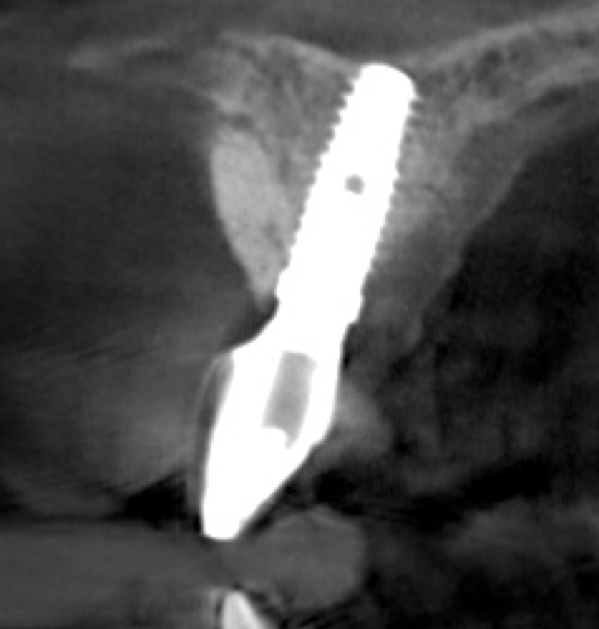

The bone graft underwent a 6-month maturation period to allow integration of the biomaterial. At this point, teeth Nos. 6 and 8 were atraumatically removed, and implants were immediately placed into the extraction sites without elevating a flap (Figure 19 through Figure 21). The gingival tissues exhibited a moderate degree of inflammation as a result of the difficult access for oral hygiene procedures under the post-orthodontic splint, which at the time had remained in place for 9 months. Implants featuring a tapered design were selected, and excellent primary stability was achieved (Figure 22 and Figure 23). Insertion torque values in excess of 45 Ncm were recorded for both implants, which allowed an immediate loading protocol.6,7,63,64